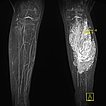

Die koronare T1-gewichtete native MRT zeigt eine intramuskuläre, gefäßreiche Läsion (isointens zur Muskulatur) mit deutlich zwischengelagertem hyperintensem Fettgewebe, mehr als bei einer normalen venösen Malformation üblich.

In der kontrastmittelunterstützen MR-Angiographie (MIP) zeigt sich ein komplettes Enhancement der venösen Malformationskomponente in der linken Wade mit Kontrastmittelpooling.